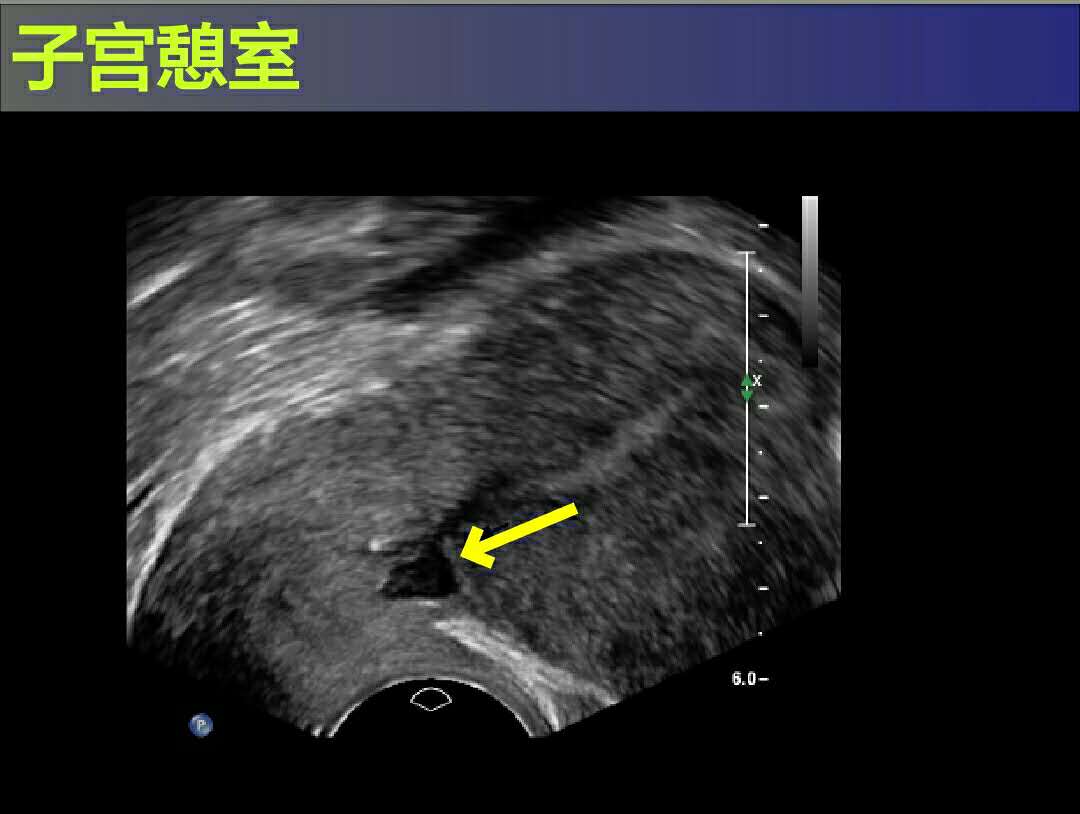

最后,王女士实在无法忍受,才到门诊就诊。医生为她做了妇科检查,排除宫颈引起的出血后,接下来便为她开了彩超检查。彩超发现原来在王女士的剖宫产手术的子宫疤痕处形成了一个憩室,也就是“剖宫产切口憩室”,这个小憩室也就是王女士长期以来月经淋漓不净的罪魁祸首。所谓憩室,就好像是平整的屋顶上凸出去的小小阁楼,每个月就负责把部分月经血留在阁楼里,细水长流,这就导致了为什么会滴滴答答十几天不干净了。

女性的子宫,形状好比是个倒置的梨子(不是矮胖矮胖型哦,是那种细长细长型),剖宫产的子宫切口在孕晚期的子宫下段,就好比是梨子体部的下方,在这个地方取切口,是因为肌层被充分的拉伸较薄,具有出血少损伤小的优点。